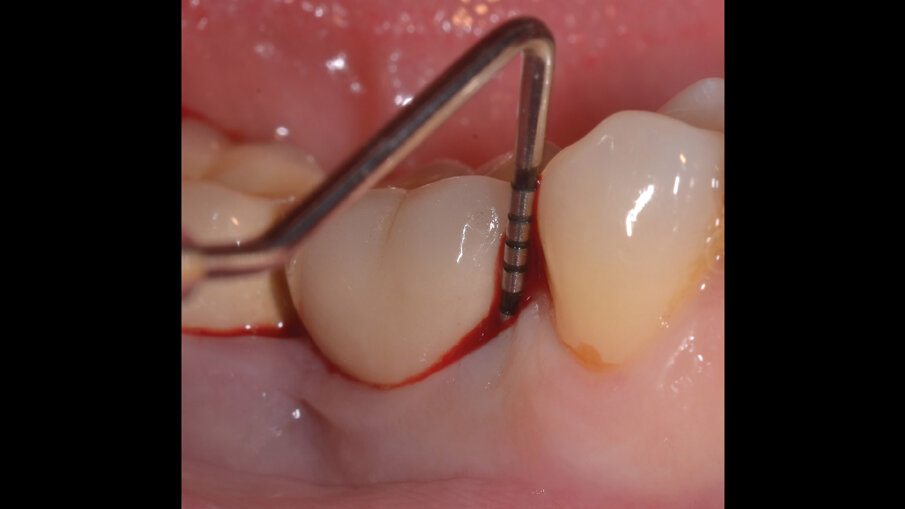

Il paziente, di sesso maschile e di 48 anni di età, è in buone condizioni di salute generale ma, a distanza di 10 anni dall’inserimento, presenta due impianti endossei, in posizione 4.6 e 4.7 con uniforme perdita ossea e con sondaggi di profondità variabile tra 6 e 9 mm accompagnati da sanguinamento, con tessuti marginali che mostrano importanti aspetti infiammatori, causa di sintomatologia dolorosa per il paziente (Figg. 1a-f).

I siti interessati sono stati strumentati per via non chirurgica, utilizzando strumenti manuali, strumenti ultrasonici e air polishing con eritritolo. Al termine della seduta è stato applicato il gel di ozono (Ozosan Gel - Bioactiva) all’interno delle tasche, lasciando agire il dispositivo per 8 minuti, quindi eseguendo lavaggio con soluzione fisiologica. Il post-operatorio ha avuto un decorso privo di dolore con rapida remissione della sintomatologia soggettiva. Il paziente è stato inserito in un programma di mantenimento parodontale trimestrale. A distanza di 6 mesi dal trattamento non chirurgico della perimplantite, i siti si presentano stabili con profondità di sondaggio ridotta tra i 3 e i 5 mm con assenza completa di sanguinamento al sondaggio (Figg. 1g-m).